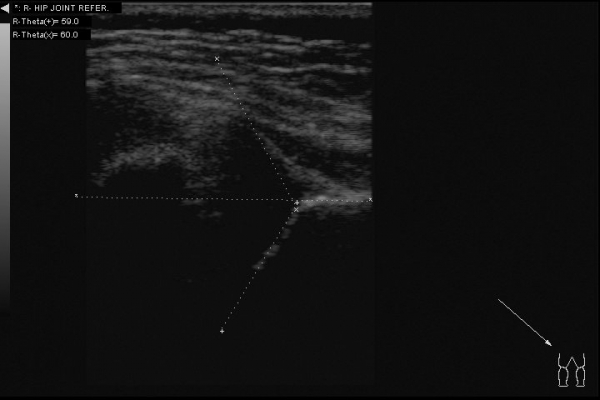

Доброго всем дня. Интересный случай сегодня: клинически у ребенка (2,5 месяца) все нормально -- отведение в полном объеме, ротация -- норма. Складки -- симметрия. Но!!! В анамнезе у мамы ребенка врожденный вывих бедра. Решил выполнить УЗИ:

Таким образом видим полное соответствие УЗИ картины -- рентгенограмме.